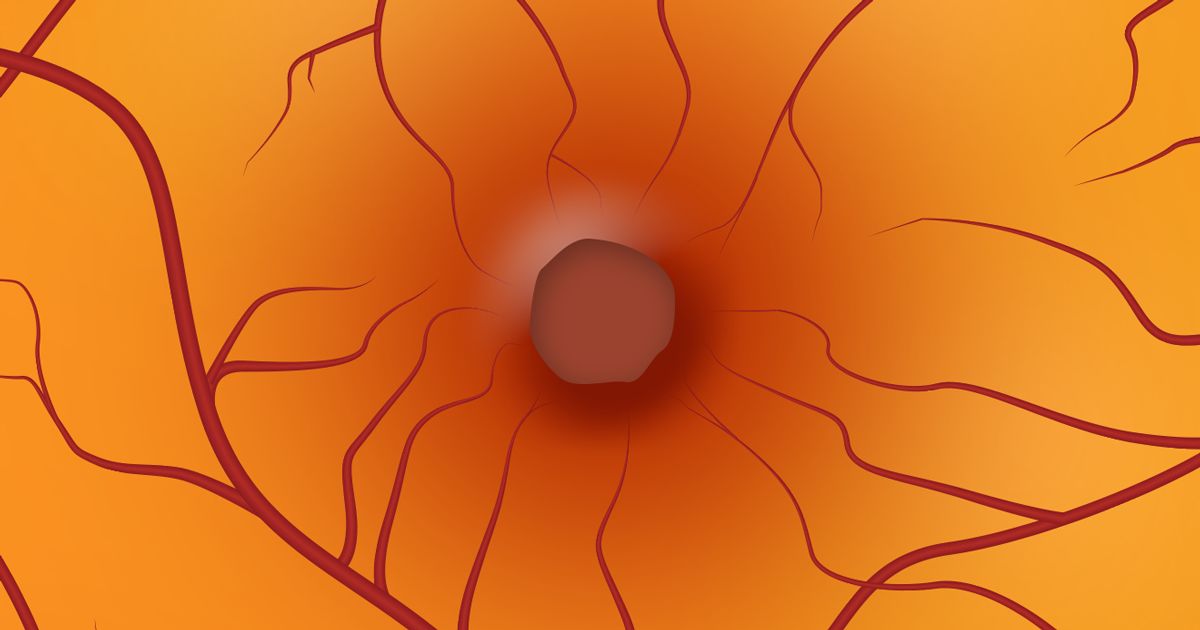

Die Makula (oder Macula lutea) ist eine sehr kleine Stelle in der Mitte der Netzhaut. Sie ist der empfindlichste Teil der Netzhaut. Die Makula ist für die Sehschärfe, das detaillierte zentrale Sehen (z. B. zum Lesen, Autofahren und Erkennen von Gesichtern) und das Farbensehen verantwortlich.

Die Makula ist voll von lichtempfindlichen Sinneszellen, den Zapfen. Der Rest der Netzhaut besteht hauptsächlich aus lichtempfindlichen Zellen, den Stäbchen. Die Stäbchen "sehen" Grau- und Schwarztöne, erkennen Bewegungen und sind für das periphere Sehen verantwortlich.

Ein Makulaloch ist ein kleiner Bruch in der Makula, der verschwommenes und verzerrtes zentrales Sehen verursacht, das normalerweise plötzlich auftritt.